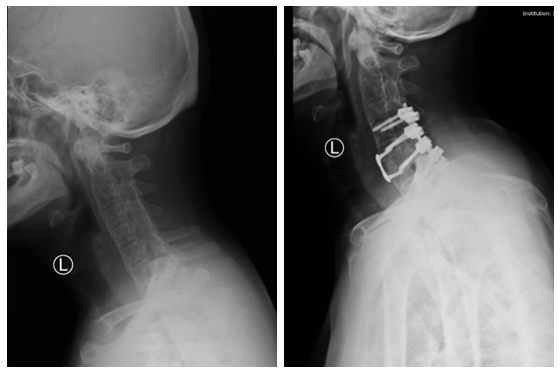

手术前后对比图

患者入院后,骨科常德病区迅速将影像资料上传至中南大学湘雅医院骨科,脊柱外科专家吴天定副教授第一时间评估患者得出结论:考虑该患者颈椎骨折脱位不稳定,合并有强直性脊柱炎、骨质量差、融合率低的特点,常规的单纯前路或者后路固定融合无法保证颈椎的融合和稳定性,需通过前后路手颈椎术给予坚强的内固定,重建颈椎稳定性,保证颈椎复位稳定质量,提高颈椎融合率,从而为保障神经功能正常创造条件。其次,颈胸交界区术中透视困难,术中极易损伤椎动脉导致大出血,再加上脊柱小关节的融合(竹节样)改变,失去了术中可参考的解剖标志,所以该手术难度高、风险大。

吴天定副教授根据患者资料制定了详细手术方案。骨科常德病区在完善相关术前准备后,1月21日,吴天定副教授到达常德,为患者实施“颈椎前后路联合复位内固定融合术”。该手术一次性完成颈椎复位、神经减压及稳定性重建,未出现任何并发症,术后3天患者即可佩戴支具下床活动,恢复效果显著。